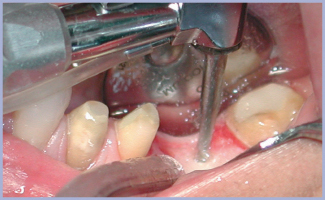

Dopo avere allestito il lembo a spessore totale (figg. 2, 3), si preparano due alveoli chirurgici, uno per l’impianto che sostituirà la radice mesiale, orientato in modo tale da risultare in asse con i carichi funzionali che si creano nella fase di entrata del ciclo masticatorio ed uno che sostituirà la radice distale, orientato in asse con i carichi funzionali che si creano nella fase di uscita. Poiché è necessario intaccare la corticale con estrema precisione, si inizia la preparazione con una fresa a palla montata su turbina (figg. 4, 5); si prosegue con il protocollo classico (figg. 6-14). Si inseriscono gli impianti, si assemblano i relativi tappi (figg. 15-19) e si sutura (fig. 20) secondo il protocollo bifase. Dopo tre mesi, quando l’osteointegrazione ha raggiunto una maturazione sufficiente ad assicurare la stabilità primaria degli impianti, si interviene con il secondo momento chirurgico per posizionare i tappi di guarigione e creare i condotti mucosi (figg. 21-24) che si epitelizzeranno in circa dieci giorni. Segue la presa delle impronte mediante transfer da impronta (figg. 25-28). Il tecnico assembla gli analoghi da gesso sui transfer, sviluppa i modelli, monta i monconi sugli analoghi ed esegue il fresaggio (fig. 29). In studio si verificano i monconi (fig. 30) e si rimandano in laboratorio per la preparazione delle cappette (fig. 31) e la relativa ceramizzazione (fig. 32).

- Fig. 4

- Fig. 5